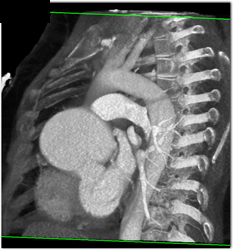

Left Upper Lobe Encased By NSCLC With Extensive Nodes